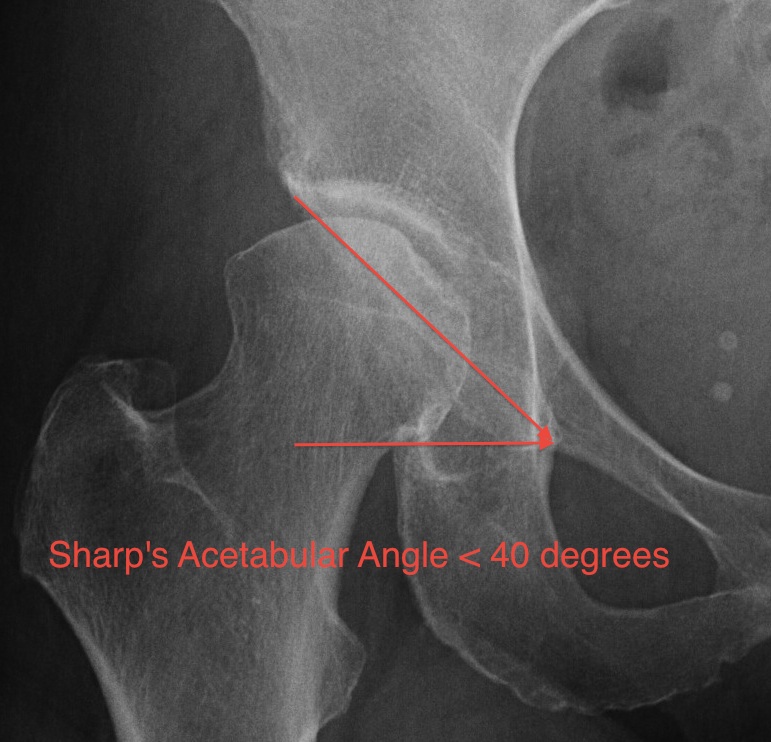

3. Sharp's Acetabular Angle 1961

- adult

- inferior tip tear drop to lateral edge acetabulum

- > 42° Abnormal